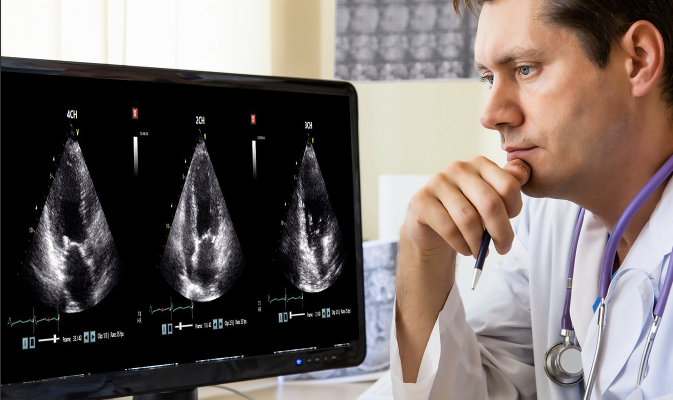

December 7, 2021 — DiA Imaging Analysis, a leading provider of advanced AI-based software for ultrasound analysis, was featured in a recent study presented by a team of cardiac physicians from Mount Sinai's Icahn School of Medicine at the American Heart Association meeting. The breakthrough study demonstrated the accuracy of LVivo RV, the company's AI for right ventricle function analysis, validating its sensitivity and specificity results compared to Cardiac MRI (CMR).

Right Ventricle (RV) size and function are vital indicators of cardiac dysfunction, including pulmonary embolism (PE), pulmonary hypertension, and right heart failure. Amid the COVID-19 pandemic, cardiac ultrasound imaging includes assessment of the RV to detect RV dysfunction, commonly seen in patients with COVID-19. Although common, RV function analysis using an ultrasound device is difficult and often requires additional examination due to the RV's challenging geometry.

The recent study of 125 patients compared DiA's right heart AI-based software to CMR. Results demonstrated high sensitivity and specificity when compared to CMR, the gold standard of cardiac imaging. The study concluded that DiA's automated AI-based right heart analysis for automated RV function quantification has the potential to accurately and instantly detect evidence of right heart dysfunction at the echo lab and near the bedside.

"We are proud to share that leading physicians from the Icahn School of Medicine at Mount Sinai, a globally ranked program, have validated our FDA-approved AI software," said Hila Goldman-Aslan, CEO and co-founder of DiA Imaging Analysis. "The study demonstrated that LVivo RV can provide an automated and accurate solution to the critical analysis of the right ventricle function using ultrasound."